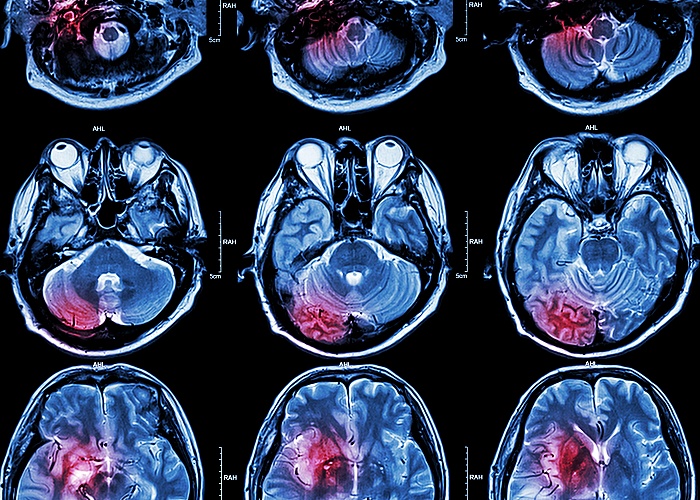

Patients with COVID-19 who suffer acute ischaemic stroke (AIS) appear to be at significantly higher risk of severe disability and death compared with stroke patients treated in the pre-COVID era, found a multicentre US study.

Numerous clinicians from stroke centres across the US and Canada have reported that a third of all patients with COVID-19 may develop neurological complications from infection, and suffer

Massachusetts General Hospital (MGH) and 29 other stroke centres say that patients with COVID-19 who experience AIS appear to be at higher risk of severe disability and death compared with stroke patients treated in the pre-COVID era.

As they reported in the Journal of Neurology, Neurosurgery & Psychiatry, slightly more than half (51%) of all patients had poor outcomes, with 39,1% dying either in hospital or within 30 days of being discharged. In contrast, data from large clinical trials conducted before the pandemic show death rates of 27,6% among all patients with ischaemic strokes, and 11, 6% among patients with strokes caused by blockage of one or more large blood vessels that supply blood to much of the brain.

“There is an interaction that is still unknown between COVID respiratory disease and stroke, because the rate of poor outcomes or mortality is clearly greater than it would be in someone who had just an acute respiratory distress syndrome or COVID pneumonia, and also worse than someone who would have an equivalently large stroke in the pre-COVID era,” said Dmytriw.